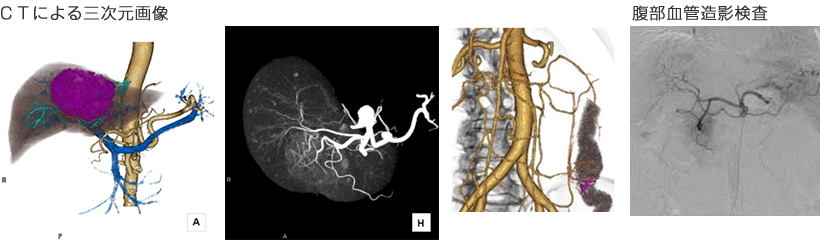

超音波とCTだけでなく、より専門的な超音波内視鏡、ERCP(内視鏡的逆行性胆管膵管造影)、PTC(経皮経肝胆管造影)、血管造影、胆道・膵管内視鏡等を行っています。